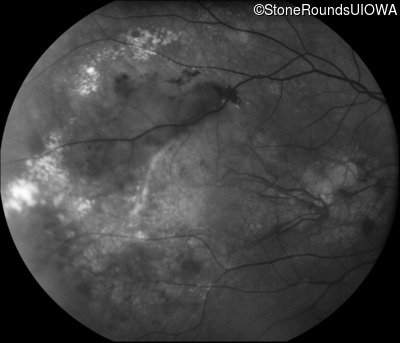

Fundus Photography - Left - 20/160 -1

Exemplar